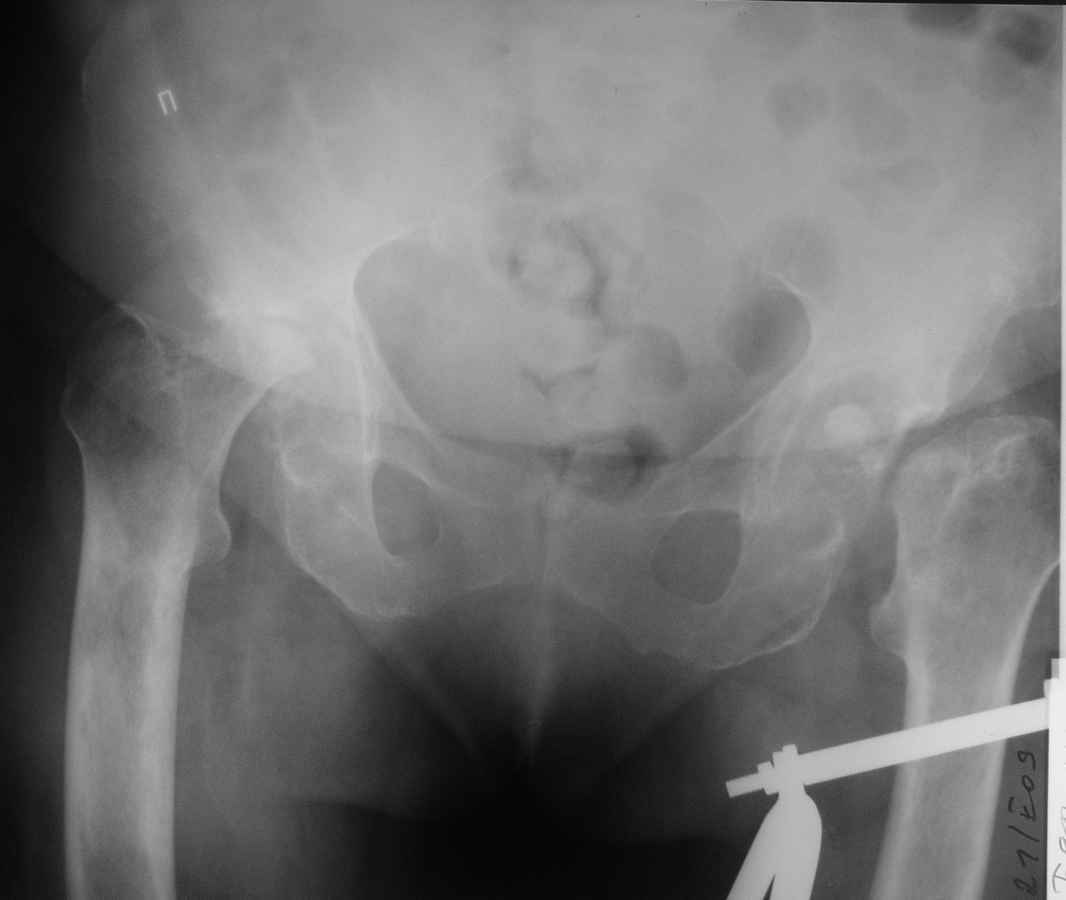

Здравствуйте уважаемые коллеги. Поступила женщина 60 лет с переломом левого бедра в н/3 диафиза, травма произошла около 2-х недель назад, упала дома. При сборе анамнеза установлено, что в течении 3-х последних лет больную беспокоили боли в тазобедренных суставах, и уже около 1,5 лет она передвигается только на сидячей каталке. При дополнительном обследовании выявлена данная рентгенологическая картина. Факт какой-либо травмы отрицает, поражения мелких и средних суставов кистей и стоп нет, в анализе крови – СОЭ – 60мм/ч, лейкоцитоза нет. Помогите, пожалуйста, определиться с диагнозом, какие исследования необходимо провести. По тактике лечения – планируем интрамедуллярный остеосинтез левого бедра, эндопротезирование тазобедренного сустава справа. После сращения бедра – эндопротезирование левого тазобедренного сустава.

Iskluchite joint infection - Rg napominaet ishod sustavnogo sepsisa, vozmozhno tuberculesa.

При неспецефической инфекционном артрите исход - анкилозирование. При туберкулезе тазобедренного сустава, как правило, поражается крыша вертлужной впадины. Скорее всего асептический некроз. Нет ли в анамнезе системного заболевания с длительным приемом ГКС, СД?

Куда девались головка и шейка бедра слева?

Рентгеновская картина шибко напоминает вторичные костные изменения при всяких неврологических делах (типа сирингомиелии) - когда эпифизы просто рассасываются. А может это идиопатический асептический некроз?

Был бы здесь инфекционный процесс, то это как-нибудь проявлялось внешне и пациентка об этом обязательно бы рассказала (т.е. был некий эпизод с лихорадкой, резким нарушением функции с последущим улучшением и т.д и т.п.).